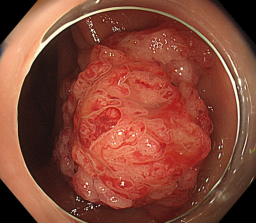

消化道早癌的病例展示(经内镜手术或活检证实):

胃角的腺癌

胃窦的微小腺癌

胃窦印戒细胞癌

十二指肠降段早癌

胃窦的腺癌 行ESD治疗

术中见较粗穿支血管,裸化后凝除,最终高效、安全的切除病灶。